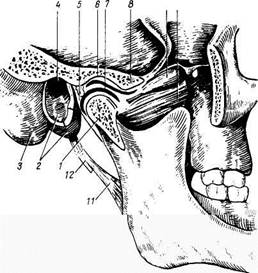

Височно-нижнечелюстной сустав, articulatio temporomandibularis (рис. 35), образуется caput mandibulae и fossa mandibularis височной кости. Сочленяю-

Рис. 35. Височно-нижнечелюстной сустав (articulatio temporomandibularis); сагиттальный распил через полость сустава.

Рис. 35. Височно-нижнечелюстной сустав (articulatio temporomandibularis); сагиттальный распил через полость сустава.

/ — caput mandibulae; 2 — pars tympanica височной кости; 3 — processus mastoideus; 4 — porus et meatus acusticus externus; 5 — capsula articularis (вскрыта); 6 — fossa mandibularis; 7 — discus articularis; 8 — tu-berculum articulare; 9, 10 - m. pterygoideus lateralis; 11 — lig. stylomandibulare; 12 — processus styloi-deus.

щиеся поверхности дополняются лежащим между ними внутрисуставным волокнистым хрящом, discus articularis, который своими краями срастается с капсулой сустава и разгораживает суставную полость на два обособленных отдела. Суставная капсула прикрепляется по краю fossa mandibularis до fissura petrotympa-nica, заключая в себе tuberculum articulare, а внизу охватывает collum

mandibulae. Около височно-нижнечелюстного сустава находятся 3 связки, из которых непосредственное отношение к суставу имеет только lig. laterale, идущая на боковой стороне сустава от скулового отростка височной кости косо назад к шейке мыщелкового отростка нижней челюсти. Она тормозит движение суставной головки кзади. Остальные две связки (lig. sphenomandibulare et lig. stylomandibulare) лежат в отдалении от сустава и представляют собой не связки, а искусственно выделяемые участки фасций, образующие как бы петлю, способствующую подвешиванию нижней челюсти.

Оба височно-нижнечелюстных сустава функционируют одновременно и поэтому представляют одно комбинированное сочленение. Височно-нижнечелюстной сустав относится к мыщелковым сочленениям, но благодаря внутрисуставному диску в нем возможны движения в трех направлениях. Движения, которые совершает нижняя челюсть, таковы: 1) опускание и поднятие нижней челюсти с одновременным открыванием и закрыванием рта; 2) смещение ее вперед и назад и 3) боковые движения (ротация нижней челюсти вправо и влево, как это бывает при жевании). Первое из этих движений совершается в нижнем отделе сустава, между discus articularis и головкой нижней челюсти.

Движения второго рода происходят в верхнем отделе сустава.

При боковых движениях (третий род) головка нижней челюсти вместе

с диском выходит из суставной ямки на бугорок только на одной стороне,

тогда как головка другой стороны остается в суставной впадине и

совершает вращение вокруг вертикальной оси.

Возможны небольшие круговые движения в 3 плоскостях.

Сосуды и нервы: сустав получает питание из a. maxillaris. Венозный отток происходит в венозную сеть — rete articulare mandibulae, которая оплетает височно-нижнечелюстной сустав, и далее — в v. retromandibularis.

Отток лимфы осуществляется по глубоким лимфатическим путям в nodi lymphatici paro-tidei и затем в глубокие шейные узлы. Иннервируется сустав из п. auriculotemporalis (из III ветви п. trigeminus).